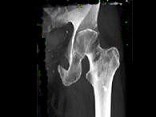

- 单项选择题患者50岁,可能性最小的诊断是 ( )

A、骨纤维结构不良

B、转移瘤

C、软骨肉瘤

D、骨髓瘤

E、以上都不是